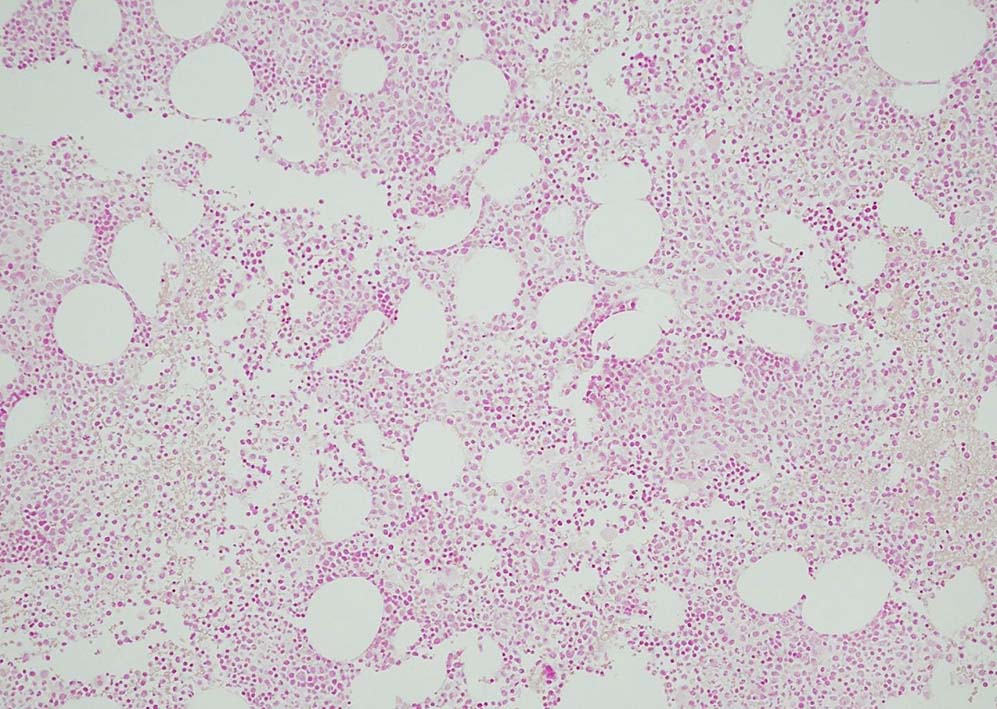

80歳代男性. 徐脈で治療中, 末梢血で血球異形成を指摘される. Hb8.8g/dl, RBC 402x104/μl, MCV 76, WBC 2500/μl, Plt. 3.9x104

Megakaryopoiesis; Mgkは増加している. 多数の分離円形核巨核球が出現している. microMgkが増加している.

Myelogram: M/E = 1.77,Blast-M 5.2%, promyelo 7.0%, Myelo 11.4%, Meta 10.0%, Stab 5.4%, Seg 18.8%, Eo mature 0.6%, Ba mature 0.6% Mo 3.0%, Lympho 4.4%, Plasma 0.2 骨髄WT1 R 1.1x104